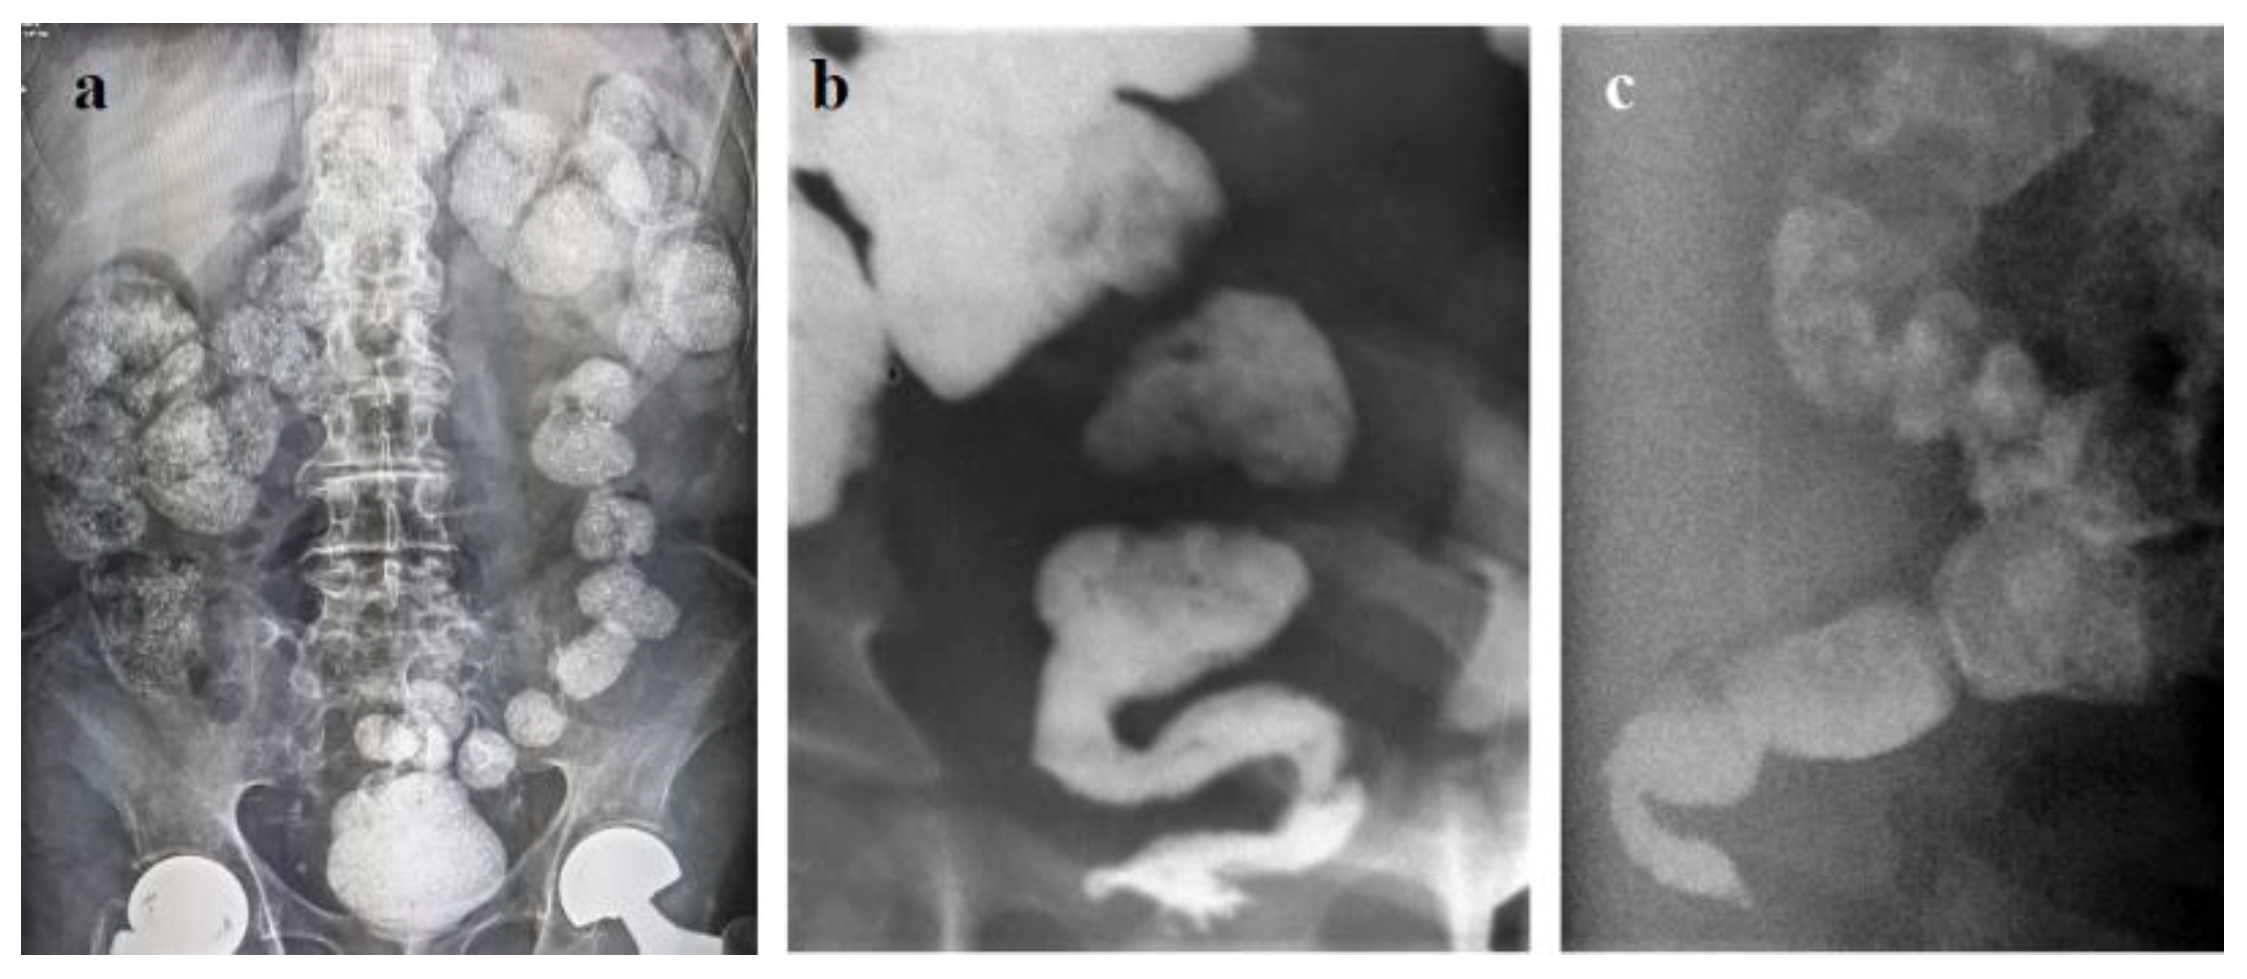

- Levin MD. The dolichosigma partially located on the right: How justified is the concept of the right slow transit constipation? World J Nucl Med. 2019 Dec 18;18(4):440-442. [CrossRef]